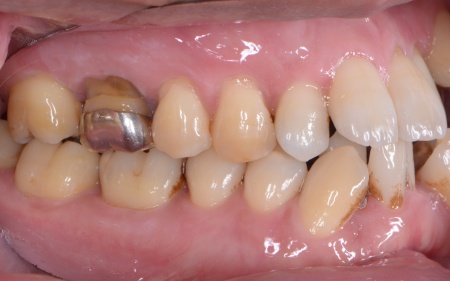

| カウンセリング | 拝見したところ、上下の歯は、ずれたりねじれたりしてデコボコに生えており、著しく歯並びが乱れていました。

またレントゲン撮影をして確認すると、右上前歯は顎の骨の中に埋まっている骨性埋伏(こっせいまいふく)の状態でした。 さらに、左下奥歯は重度の歯周病であり、歯を支えている骨が一部溶けていることが判明しました。 以上のことから、歯並びを整える矯正治療と歯周病の治療を併せて行う必要があると診断しました。 |

①抜歯をしてから歯並びを整える「抜歯矯正」 今回のケースでは、左上下の奥歯各1本(第3大臼歯)、右下の奥歯1本(第3大臼歯)、左上下と右下の奥歯各1本(第1小臼歯)の計6本の抜歯が必要です。 また、奥歯の噛み合わせは正常だったことから、それを維持しながら歯並びを整えるために以下の方法を採用します。 ②矯正治療後、歯周病を発症している左下奥歯(第1大臼歯)を温存するために、失われた骨や歯茎を再生する「歯周再生療法」を行う まずは歯の移動スペースを確保するために、計6本の歯を抜きます。 矯正治療終了後、歯の後戻りを防ぐため、上下前歯の裏側にワイヤーを接着して固定させる「フィックスリテーナー」を装着しています。 その後、左下奥歯に歯周再生療法を行って歯周病が改善したことを確認し、治療を終了しました。 |